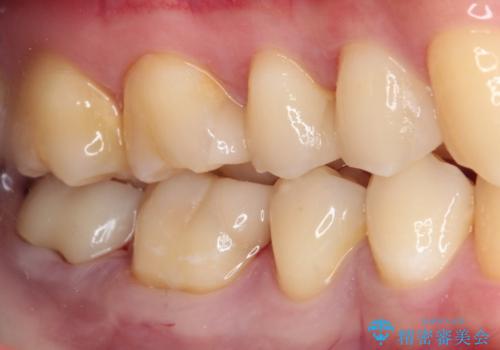

詰め物が外れた セラミックインレー修復

- 以前治療した詰め物が外れてしまい、冷たいものがしみることを主訴として来院された患者様です。

むし歯がないことを確認し、セラミックインレーにて修復するととしました。

適合の良いセラミックインレーの装着により、冷たいものがしみる症状はなくなりました。